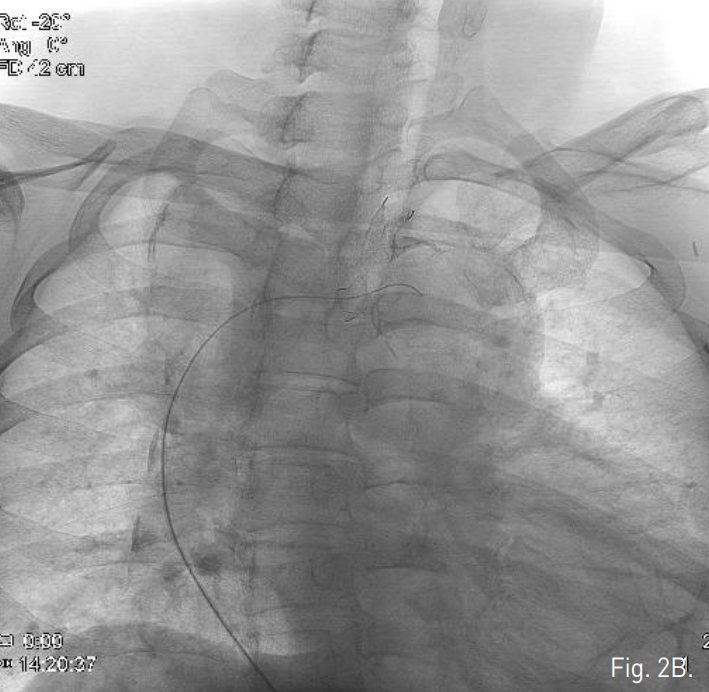

우측 대퇴동맥을 천자하여 8F vascular sheath를 삽입한 후 5F pigtail catheter를 이용한 대동맥조영술에서 하행대동맥에서 기시하는 aberrant left subclavian artery의 분지부 근처에 이전에 삽입한 stent-graft의 중간 부위에서 외측으로 aneurysm sac이 조영됨(Fig. 2A). 0.035-inch 유도철사가 stent-graft를 통과하여 aneurysmal sac내 들어가는 것으로서 stent-graft의 tear 및 type Ⅲ endoleak임을 확인함(Fig. 2B). Stent-graft의 metal component의 fracture는 없었음.

Fig. 2

B. A 0.035-inch guidewire was advanced into the aneurysm sac, through the stent graft, suggesting type III endoleak.